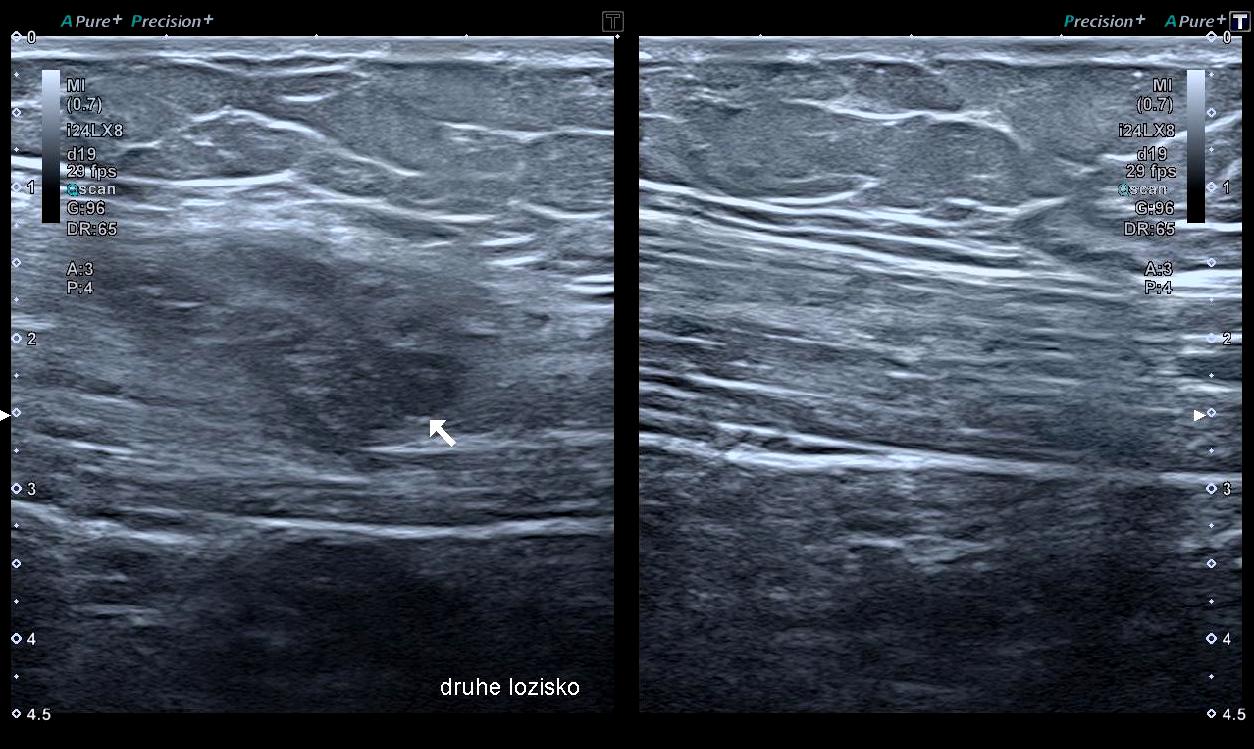

Pacientka, 32letá žena, si stěžovala si na bolest břišní stěny dole vlevo v oblasti jizvy, která se občas šířila do sakrální oblasti. Tyto bolesti se začaly objevovat zhruba rok po císařském řezu a postupně se staly intenzivnějšími. Pacientka po čase vypozorovala, že bolest souvisí s jejím menstruačním cyklem. Také trpěla mírnou bolestí po fyzické aktivitě, jako je běhání, cvičení v tělocvičně nebo zvedání těžkých předmětů. Předchozí rehabilitační péče zaměřená na uvolnění jizvy bohužel nepřinesla žádný efekt. Zhruba rok a půl po císařském řezu se bolest v dolní části břicha zhoršila a byla výrazněji lokalizována na levé straně. V tom důsledku pacientka přestala sportovat přibližně dva roky po císařském řezu. Péče fyzioterapeuta zaměřená na obnovení mobility měkkých tkání v dolní části břicha a obnovu aktivity břišních svalů, přinesla pouze částečné výsledky. Bolest v dolní části břicha a v oblasti jizvy se postupně zhoršovala, až se stala trvalou součástí života pacientky. Ta trpěla bolestmi více než dvě třetiny měsíce. K samoléčbě používala nesteroidní antirevmatika, často ve spojení s alkoholem. Přibližně po třech letech od císařského řezu se stav pacientky stále zhoršoval. V té době byla vyšetřena fyzioterapeutem specializujícím se na muskuloskeletální sonografii. Sonografické vyšetření odhalilo dvě léze v oblasti břišní stěny. Jedna, větší, se nacházela v blízkosti jizvy po císařském řezu a druhá, menší (Obrázek 1), byla umístěna přímo v levém přímém břišním svalu. Tyto nálezy ve spojení s anamnézou vedly k podezření na endometriotická ložiska v břišní stěně. Následně byla pacientka odkázána na specializované gynekologické centrum a informace byla předána i praktickému lékaři.

Obrázek 1; Jedno z ložisek endometriózy lokalizované v m. rectus abdominis (vlevo). Pravá, zdravá strana, kde je stejný sval intaktní, pro porovnání (vpravo).